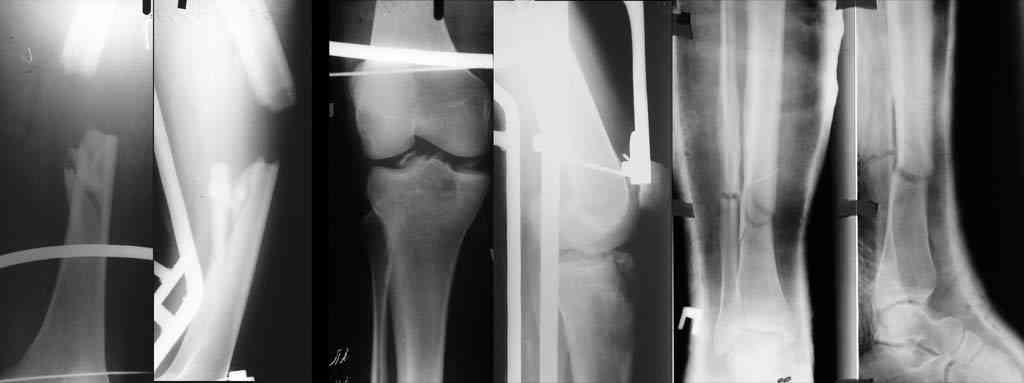

К нам переведен больной 36 лет (175 см рост, 105 кг масса тела), который 64 дня назад в ДТП получил множественную скелетную травму: перелом вертлужной впадины справа с задним вывихом бедра и повреждением крестцово-подвздошного сочленения справа, оскольчатым (тип C3) переломом диафиза правого бедра на границе с/3 - н/3, открытый (тип III В по Каплану-Марковой) краевой перелом мыщелков правой большеберцовой кости, закрытый поперечный перелом диафизов костей правой голени на границе с/3-н/3 (т.е. все повреждения справа). Судя по анамнезу, имело место сдавление правой голени и бедра около 1,5 часов. В ЦРБ (по месту получения травмы) был доставлен в тяжёлом травматическом шоке, отмечались признаки ОПН (в частности, олигурия и подъём уровня креатинина выше 300 ммоль/л). Судя по анамнезу, более месяца сохранялся резко выраженный отёк правого бедра. Из выписки известно, что безуспешные попытки закрытой репозиции вывиха бедра были выполнены при поступлении в ЦРБ. Больному также выполнен накостный остеосинтез диафиза правого бедра. Рана зажила первичным натяжением. Голень фиксирована гипсовой повязкой. В области правого коленного сустава остаётся обширная рваная рана с дефектом кожи (до 20x20 см), частично закрытая дерматомными лоскутами, из которой высевается полирезистентный acinetobacter. Продолжает эпизодически лихорадить (до 38), сохраняется лейкоцитоз (11-14 тыс), в ряде анализов крови отмечался сдвиг до миелоцитов (1-6%). В остальном - без видимой патологии. Отёк бедра в настоящее время незначительный. После перевода наложено вытяжение за бедро 12 кг. Хотелось бы узнать мнения о вариантах тактики лечения перелома вертлужной впадины и вывиха бедра (учитывающие и давность травмы, и сопутствующие повреждения). Хотя этот нюанс совсем немедицинский, но замечу, что больной не настроен на любые виды платной медицинской помощи. Имеющиеся рентгенограммы и КТ приложены. С уважением Игорь

К сожалению, отправить все снимки и КТ сразу не получилось. Дополняю.

Действительно, картинка с пластинкой делает сращение вообще сомнительным, так что эндопротезирование может отложиться на неопределенный срок. Надежнее пластинку из бедра убрать малонвазивно, и закрыто бедро заштифтовать.

Надо прикинуть, может быть перелом настолько низкий, что с недлинным ретроградным стержнем останется достаточно места для ножки протеза. И можно будет сделать первичное протезирование из положения как есть сейчас.

Учитывая перелом задней стенки верл.впадины из доступа Кохера-Лангенбека репозиция-фиксация таза-вправление вывиха-синтез впадины.Фиксация таза на уровне передней и задней колонн во избежании ротационных смещений.Удаление пластины и реостеосинтез бл.штифтом-согласен.

Скорее всего перелом Т-образный и головка вроде бы цела. Я бы разобрал впадину и собрал обратно с фиксацией трансфрактурными винтами передней колонны и мостовидной пластинкой задней. Перед открытой реконструкцией возможно наложил бы аппарат таз бедро для низведения головки, если пластина на бедре выглядит надежной.